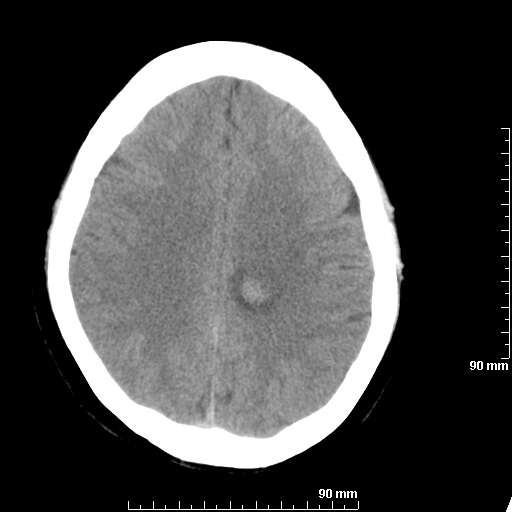

[维修案例解析] 大家猜猜看,这个伪影是怎样产生的.

二马日王 显示全部楼层 发表于 2011-6-9 18:12:55 |阅读模式

我院西门子单排CT由于一零件受损而产生的伪影.

哈哈,都不是。是虑线器fiter裂损。大家没想到吧。

哦,跟脑出血有点像哦

形状不规则,边缘模糊。比较特殊的一种伪影哈!

这种伪影很常见!伪影应该是在视野的中心的。

西门子的虑线器fiter裂损这才是很难见的问题,GE的最常见

虑线器老化,中间崩裂一块掉了